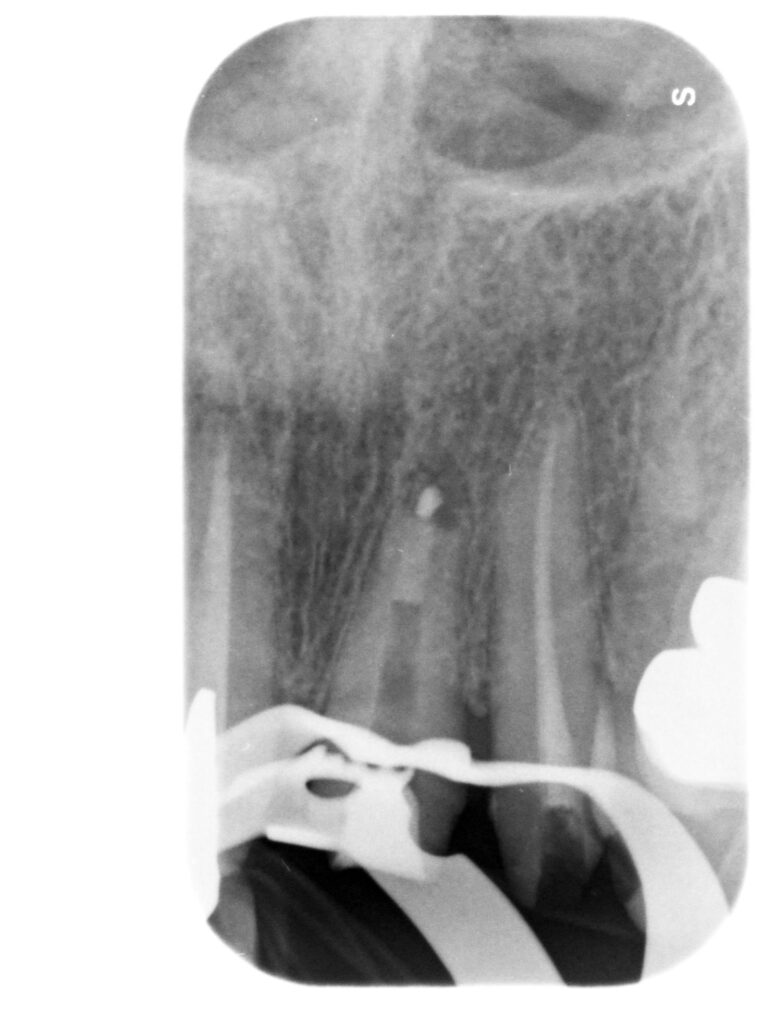

Caso clinico – ritrattamento ortogrado con apical plug in MTA